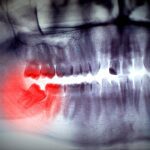

Getting a tooth pulled can often seem like a harrowing experience. After all, a lot of people would prefer to avoid the dentist if possible. However, if a tooth is in a condition in which extraction is the best course of action – to prevent infection, pain and further decay – then going to the dentist is certainly the best decision you can make. Extracting wisdom teeth, too, is a necessary, natural surgery.

A dry socket can be painful and send you right back to the dentist. The hole, or socket, left behind from the tooth extraction is essentially an open wound. Food debris that gets lodged in this socket may cause inflammation or infection because the nerve endings and jaw bone are unprotected and at easy risk of being damaged.